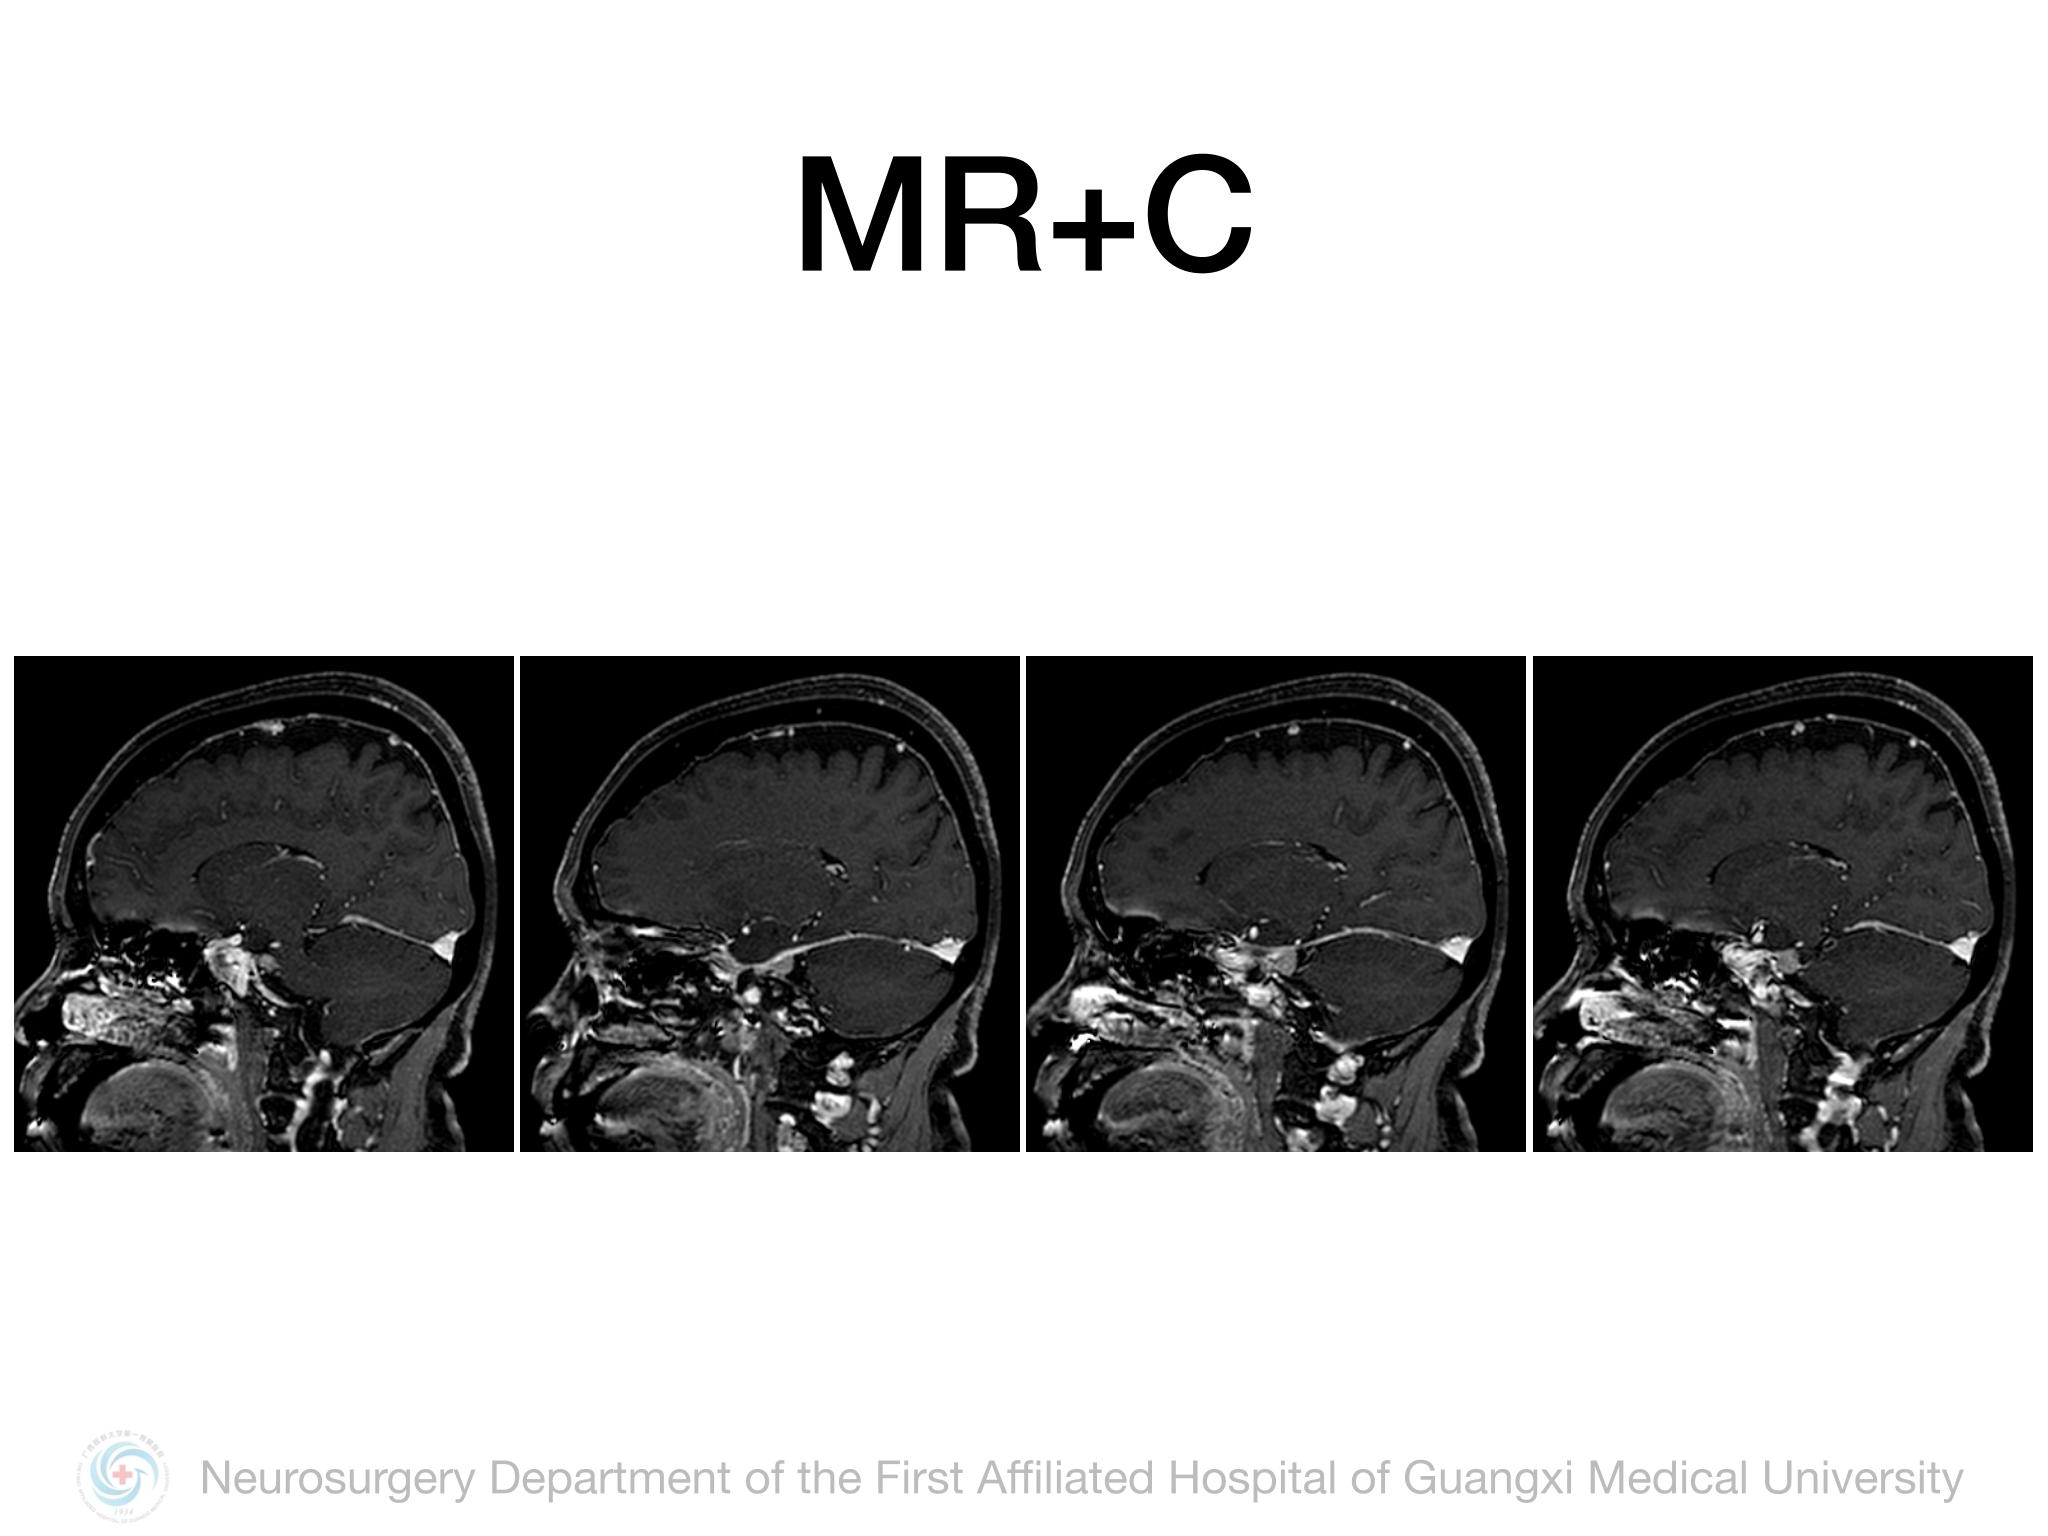

Meckel’s cave(MC)由多层硬膜围绕三叉神经半月结构成,通过三叉神经门与后颅窝蛛网膜下腔相通,起源于MC的脑膜瘤并不常见,文献报道约占所有颅内脑膜瘤的1%。Samii教授报道将MC脑膜瘤分4型,I型:局限于MC;II型:MC脑膜瘤向中颅窝扩展或海绵窦浸润;III型:MC脑膜瘤向CPA区扩展;IV型:MC脑膜瘤向中后颅窝均有扩展。本例属于I型,局限于MC,因此首选颞下经天幕入路,结扎岩上窦,显露部分岩尖,必要时硬膜下磨除岩尖。术中需注意颞叶及Labbe静脉壁保护,避免损伤岩静脉,尽可能全切肿瘤及基底。本例术中见肿瘤基底位于MC外侧壁及顶壁,主体位于MC,向后下推挤三叉神经,向后颅窝有部分延伸,但与脑干无黏连,向三叉神经内侧进入MC内侧空间,充分显露MC后将肿瘤及其基底全切,周围神经血管保护良好,术后无新发神经功能障碍,疗效满意。